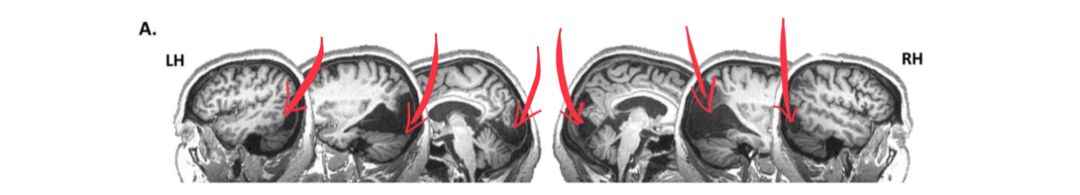

可是为啥在核磁上面看,脑梗侠的初级视皮质v1-v3、以及外部区域hV4,V3A,V3B,LO1-2和VO1都受损了,阿姨还能“看见”呢?

我们再来深入了解了解视皮质:

在接收到外侧膝状体传来的信息之后,投射到后脑勺枕叶的视皮质来,更具体一点来说,投射到的是初级视皮质——v1——这个纹状皮层(Striate cortex)。但是在v1之上的其余不少枕叶皮层也涉及了视觉处理,比如v2-v4这几个外纹状皮层。

按照现有研究,v1处理简单视觉,v2是处理图形与轮廓,v3更多的在传递信息,v4对颜色觉有关。

登录/注册后可看大图

随着研究的深入,功能性以及结构性的核磁成像终于让“脑梗侠”阿姨的秘密渐渐浮出水面:MT(颞中运动复合体)有着引人注目的强大、备用功能,功能和结构MRR双侧地揭示了中间时间运动复合体(MT+)的强大且可靠的备用功能。并且看样子MT还负责包揽了“脑梗侠”阿姨识别运动方向的功能。不过尽管做了很多测试,科学家依然无法发现,在给MT传递信息的初级视皮质都死翘翘的情况下,MT是怎么自助工作的~

你瞅瞅,看到动态的棋盘,这家伙给“脑梗侠”阿姨的MT乐的,直“冒火光”(图中橙色区域为强烈激活的MT)~